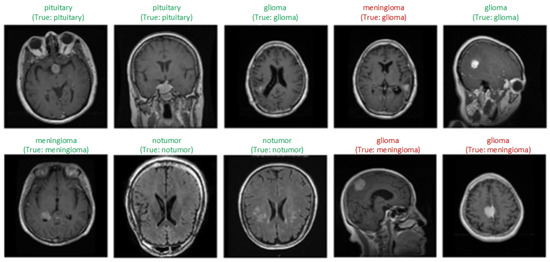

Figure 5 shows samples of each class obtained as a result of the classification of MRI scans by the model. Labels expressed as “True” indicate the actual class of the image, and the one above shows the class label predicted by the model. Green labels show correctly classified samples, and red labels indicate incorrectly classified samples. Three samples whose classes were incorrectly predicted by the model and some correctly classified samples are visualized. The model generally classified the images correctly. Misclassifications may be due to the similar structural features of tumors.

Figure 5.

Prediction results of proposed model.